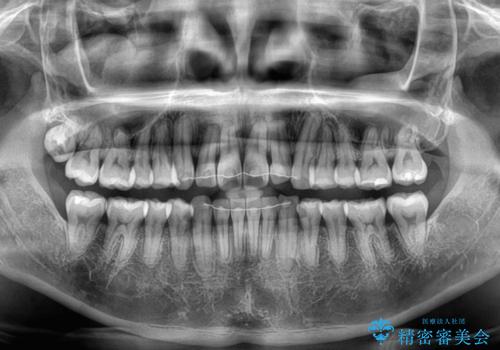

- 上下前歯のデコボコとクロスバイトを気にして来院された患者様です。

インビザラインを用い、IPR(歯と歯の間を削る)と歯列全体を拡大させることで、歯並びを整えていくこととしました。

毎日22時間の装着時間を徹底してくださったのですが、左右ともに臼歯が咬合しなくなるという、インビザライン独特の症状が強く長く続いてしまい、終了するまでに長期間を要してしまいました。